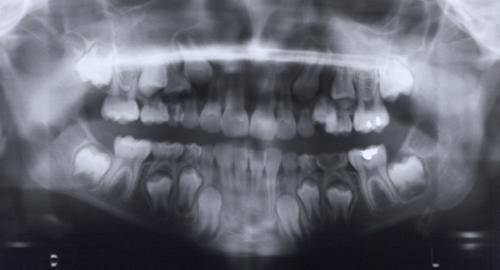

La radiographie est une technique employée aussi bien préventivement (exemple : mammographie de contrôle) que pour réaliser un diagnostic (exemple : radiographie dentaire, Figure 2) mais aussi pour l’accomplissement d’un acte thérapeutique (exemple : kystographie gazeuse).